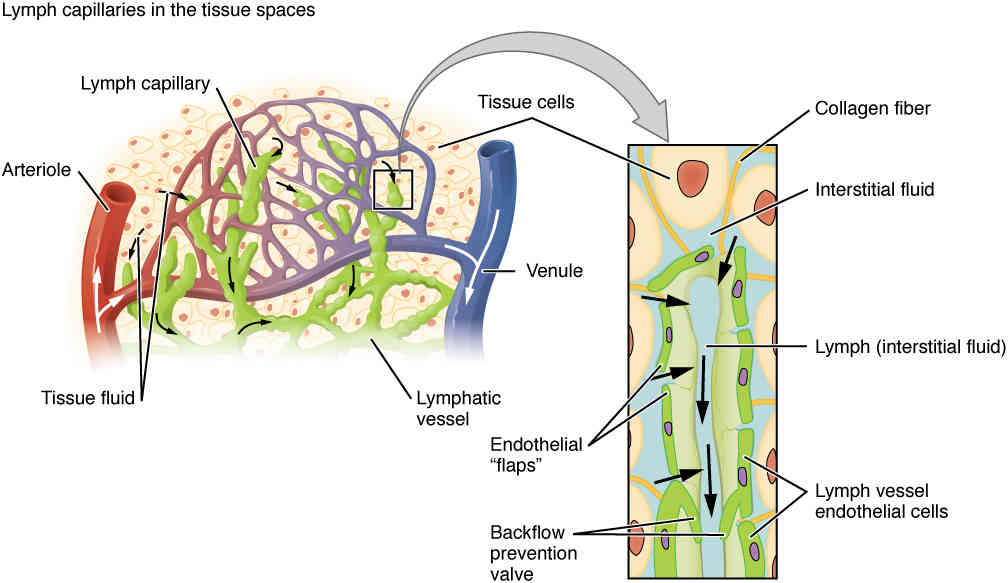

This page is under construction. For now, it is just a resource of the images found in the OpenStax Anatomy and Physiology Handbook. It wil slowly change into a revision tool. Each slide has a number. Use this to refer to the slide. When completed, it will have an unlabelled section, with labelled slides in parallel. On the unlabelled slides, write your answer and use the labelled slide to assess yourself. Keep track by also noting the number on each slide. Improvement at each attempt is important, more so than full marks on a first attempt.